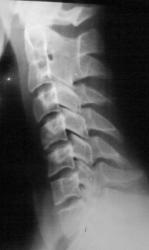

Во время служебного задания. сотрудник ЧОПа получил травму - удар в голову.

При обследовании был выявлен прелом С2

Извините перелома не вижу, наверно утомился.

Синостоз, понятно, а где перелом?

поставил доктор, который работает на КТ. Я подходил к нему и он объяснил, что перелом определяется ввиде нарушения кортикальной пластинки слева.

Кортикальной пластинки чего? Покажите где это.

Кроме конкресценции С2-С3 ничего особенного не видно.

Похоже на краевой перелом по переднелевому контуру зуба, точно. Глазастая какая Ola-la! Смеётся

почему я показал этот снимок. Перелома я сам не нашёл, поэтому и решил посоветоваться с вами, с коллегами.

Может, с частью связки оторвалось? Вроде бы и расстояние между зубом и атлантом слева чуть шире, чем справа. А может, немного асимметрично сканы идут.

Теперь и мне что-то видится в третьем ряду на 2х кадрах справа. Кстати, такой перелом большая редкость. К счатью, относится к стабильным.

Снимки через рот вряд ли помогут, т. к. откололся маленький фрагмент по передне-боковой поверхности верхушки зубовидного отростка. Плоскость перелома параллельна фронтальной плоскости и в прямой проекции хорошо увидеть верхушку зуба на фоне затылочной кости и дуги атланта лично у меня надежд нет. Да и зачем, когда уже КТ сделали.